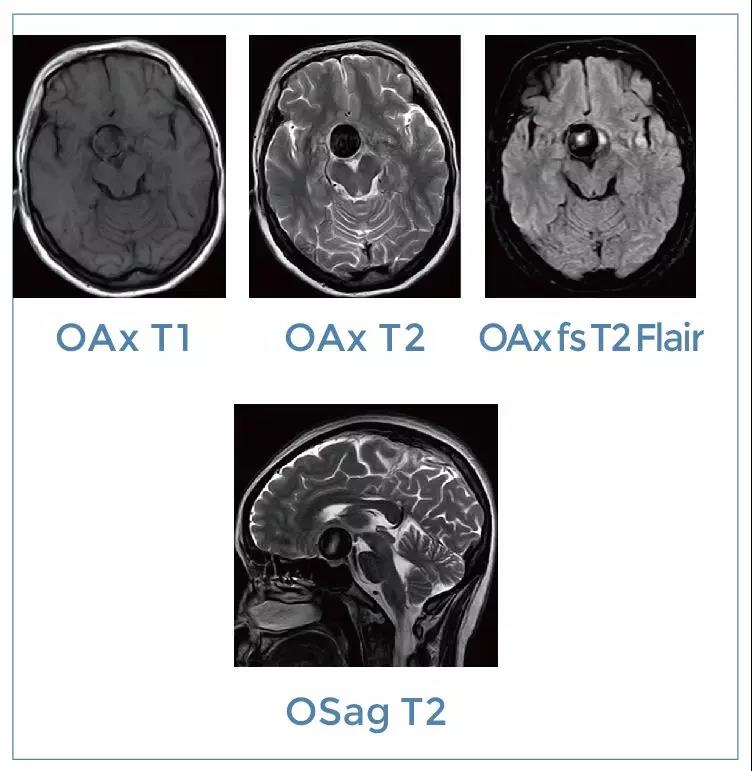

【朗润影像档案】磁共振影像病例分享(编号20200104)